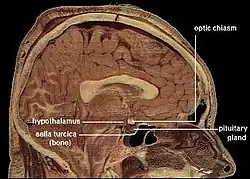

Corpus callosum from above, front part at the top of the image | |

Sagittal section of a brain, front part to the left. The corpus callosum can be seen in the center, in light gray | |

The corpus callosum forms the floor of the longitudinal fissure that separates the two cerebral hemispheres. Part of the corpus callosum forms the roof of the lateral ventricles.[5]

The corpus callosum has four main parts – individual nerve tracts that connect different parts of the hemispheres. These are the rostrum, the genu, the trunk or body, and the splenium.[4] Fibres from the trunk and the splenium, known together as the tapetum ("carpet"), form the roof of each lateral ventricle.[6]

The front part of the corpus callosum, towards the frontal lobes, is called the genu ("knee"). The genu curves downward and backward in front of the septum pellucidum, diminishing greatly in thickness. The lower, much thinner part is the rostrum and is connected below with the lamina terminalis, which stretches from the interventricular foramina to the recess at the base of the optic stalk. The rostrum is named for its resemblance to a bird's beak.

The end part of the corpus callosum, towards the cerebellum, is called the splenium. This is the thickest part, and overlaps the tela choroidea of the third ventricle and the midbrain, and ends in a thick, convex, free border. Splenium translates as "bandage" in Greek.

The trunk of the corpus callosum lies between the splenium and the genu.

The callosal sulcus is a sulcus that separates the corpus callosum from the cingulate gyrus.